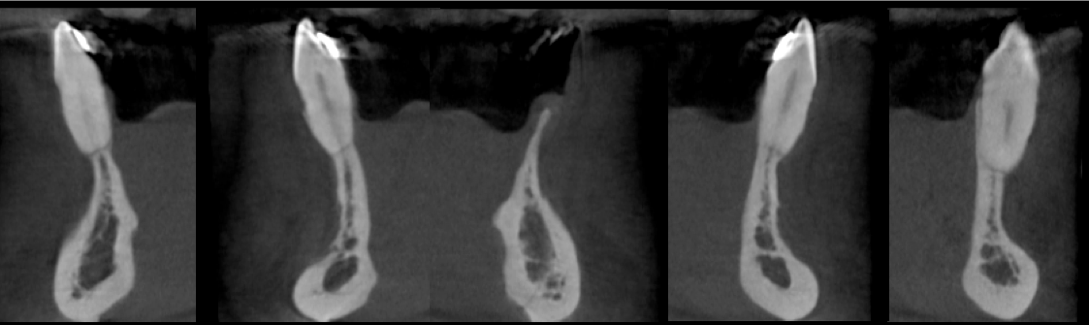

Patient suffered a traumatic injury at age 12. Five implants were placed during his early 20’s that subsequently failed. Implants were removed and repeated bone grafting procedures were unsuccessful, resulting in inadequate bone volume for implants and heavy scar formation. Patient was eventually referred to our office for augmentation of the severely maxillary anterior residual ridge.

Performed in a single office procedure using local anesthesia and two small incisions. No flaps, no tenting screws and no membranes were utilized. Sufficient horizontal and vertical bone volume was achieved to allow future placement of multiple implants.

Substantial vertical augmentation in the area of the failed anterior implants accomplished with the S.M.A.R.T. method.  The patient reported minimal pain and moderate swelling. Periosteal elevation was difficult due to extensive scar tissue.

Implants were placed 9 months following the S.M.A.R.T. bone graft. Bone in the vertically grafted areas was hard to drill through the osteotomy process. All implants exhibited excellent primary stability.